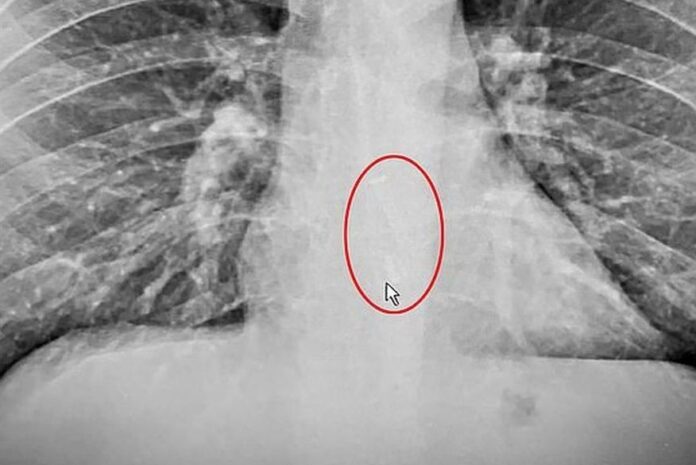

Segundo as imagens de raio-x, o earbud estava alojado em seu esôfago, e foi necessário realizar uma endoscopia de emergência para retirar o dispositivo do corpo.

Os familiares de Gauthier desconfiaram que ele havia engolido o fone, mas o mesmo não acreditou na ideia. Após relutar, procurou ajuda médica e, para sua surpresa, descobriu em um raio-x que o dispositivo estava dentro do seu corpo, alojado exatamente no esôfago.